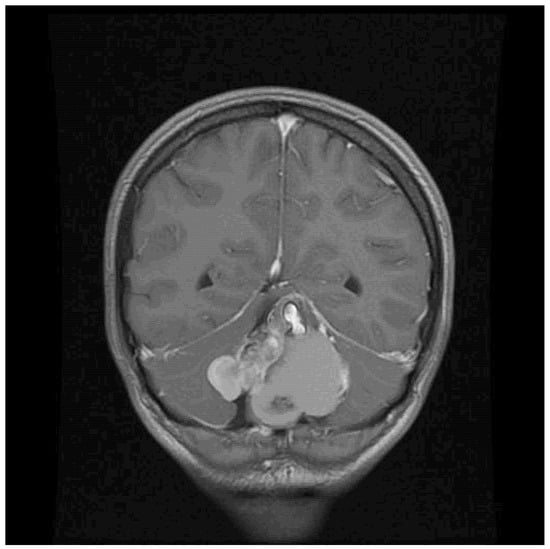

| 22/female | cerebellum—midline | mature teratoma | severe headache | current case |